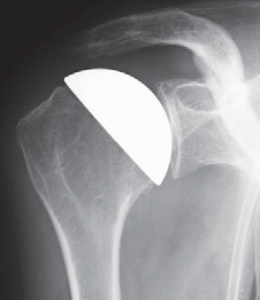

Das Schultergelenk wird häufig im Verlauf einer rheumatischen Erkrankung befallen. Die operative Therapie orientiert sich am Verlauf der Erkrankung. Im Stadium der Gelenkentzündung mit hauptsächlichem Befall der Weichteile (Gelenkschleimhaut, Gelenkkapsel, Rotatorenmanschette) ist ein arthroskopisches Debridement mit Entfernung der Gelenkschleimhaut (Synovia) und des Schleimbeutels das Verfahren der Wahl. Schreitet die Erkrankung jedoch weiter fort und greift auf den Gelenkknorpel und Knochen über, so sollte möglichst frühzeitig eine Prothese eingesetzt werden. Im frühen Stadium lässt dann eine so genannte Cup-Prothese einsetzen (Abb. 43).